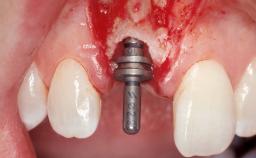

A 30-year-old female patient had lost tooth 21 and was referred to our clinic for consultation and treatment. Due to advanced apical infection, tooth 21 had been extracted two months earlier at another clinic and an acrylic-resin tooth had been bonded to the adjacent teeth. The patient desired implant treatment to avoid any damage to the adjacent natural teeth. While the patient had no history of any systemic disorder, she was a heavy smoker and exhibited medium to advanced periodontitis in the entire jaw. After the initial treatment to achieve a pocket probing depth of less than 4 mm and no bleeding on probing, a decrease in the height of the papillae mesial and distal to the extraction site and overall gingival recession were observed.

Type of Implants One-Piece|Reduced-Diameter

Bone Augmentation Horizontal|Staged

Augmentation Materials Autogenous chips|Membrane

Placement Protocol Early or late implant placement

Bone Volume Deficient horizontally, requiring prior grafting